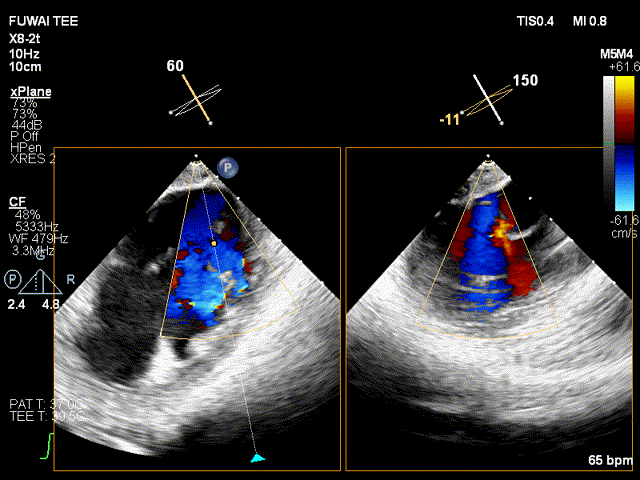

手术团队使用MitraClip®独特的三层双调弯导管,经股静脉穿刺,在食道超声引导下完成房间隔穿刺。穿刺后将导管送入左心房,对准二尖瓣目标位置P2区域。准确捕捉瓣叶,二尖瓣夹释放后,超声显示反流几近消失,患者各项生理指标正常,手术顺利完成。